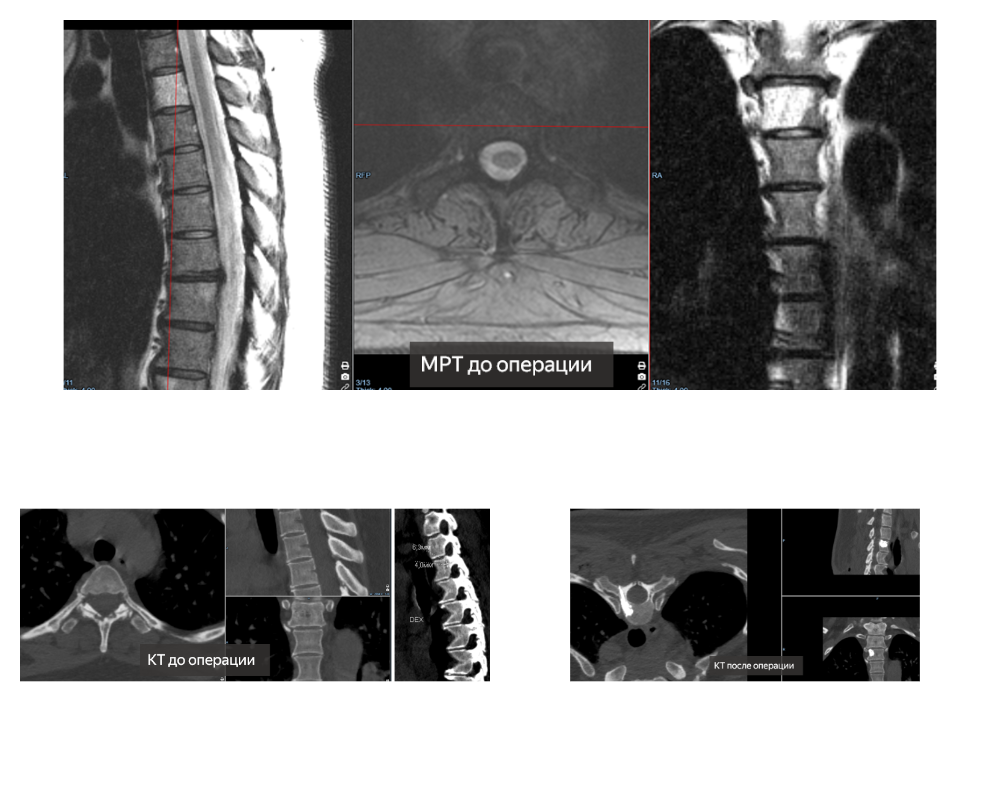

Врачи отделения №10 Клиники патологии позвоночника и редких заболеваний провели уникальную операцию - биопсию новообразования в позвоночнике молодой женщины 41 года.

Опухоль располагалась внутри тела верхне-грудного позвонка, доступ к которому имеет специфические особенности при обычном рентгенологическом контроле.

Требующее ювелирной точности хирургическое вмешательство в данном случае проходило всего полчаса благодаря интраоперационным помощникам хирургов – КТ-навигации и ультрасовременному компьютерному томографу. Операцию проводили два нейрохирурга: Евгений Матвеев и д.м.н., заведующая отделением №10 Оксана Прудникова.

- Сложность была в том, чтобы прицельно попасть иглой в опухоль и взять материал на гистологический анализ. Стояла задача – забрать фрагмент опухоли и провести вертебропластику третьего грудного позвонка.

Определение типа опухоли определяет тактику дальнейшего лечения пациентки. Предположительно, опухоль – гемангиома с нетипичной структурой и вертебропластика является вариантом ее лечения.

В случае если это метастатическое поражение, биопсия позволит нам точно понять местоположение первичного поражения. Навигационная система позволила не только прицельно войти в опухоль, но и контролировать продвижение иглы и медицинского цемента.

А о-дуга обеспечила 3D-визуализацию внутренних структур пациента в реальном времени прямо в операционной, - рассказала Оксана Прудникова.

Молодая женщина с новообразованием грудного позвонка приехала из Набережных Челнов. Определить характер новообразования по его нетипичной структуре, даже используя современное рентгеновское оборудование (КТ и МРТ) врачи не смогли.